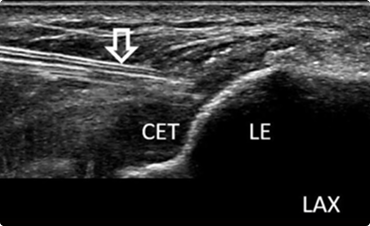

초음파 확인

통증 부위를 초음파로 정밀하게 확인합니다.